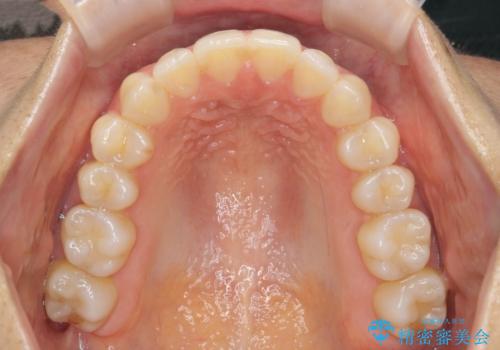

- 気になる前歯のガタつきをマウスピースで治療したいと希望され来院されました。

当日に矯正検査を行い、骨格・歯に問題がないことを確認しマウスピースによる矯正治療を進めます。

IPRを前歯部に少量行うことで、非抜歯でも前歯が外に飛び出さない仕上がりを達成できました。